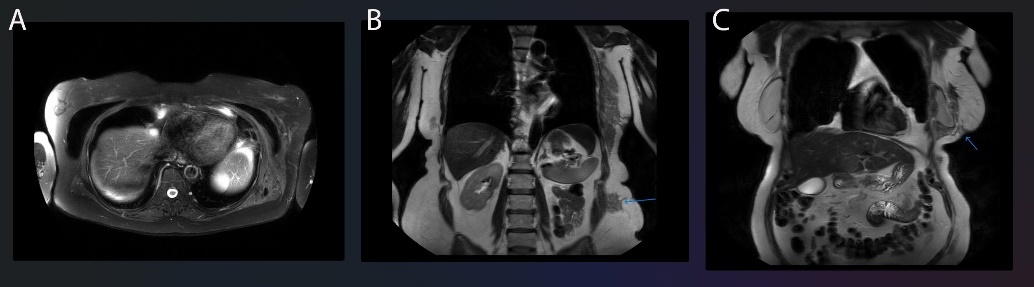

An MRI performed with gadolinium contrast and specific silicone selective sequences demonstrated extensive silicone migration along fascial planes, in a contiguous mass measuring at least 28 cm craniocaudally (Figure 1).